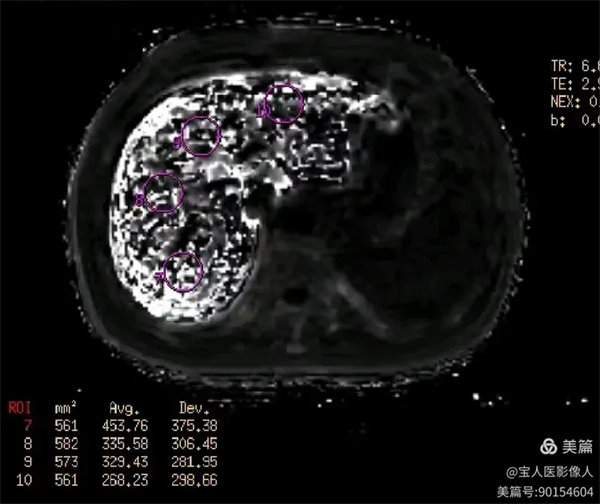

R2*圖,肝實(shí)質(zhì)信號(hào)不均勻明顯升高。

R2*圖,測(cè)量全肝不同部位肝實(shí)質(zhì)的R2*值都明顯升高。